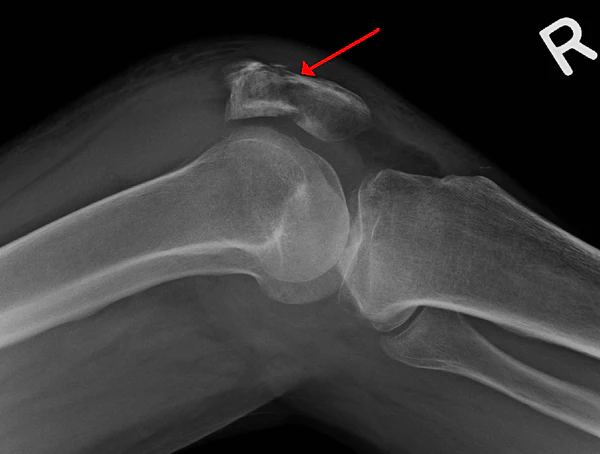

- Рентгенография коленного сустава двух проекциях

Известно множество классификаций переломов надколенника. Классификация переломов разнообразна и основана характере перелома и степени смещения его отломков. Переломы делятся на: без смещения (диастаз до 2—3 мм) и со смещением (диастаз более 3 мм или при неконгруэнтности суставной поверхности более 2 мм). Морфологически разделяют на поперечные, продольные, звёздчатые (оскольчатые) и отрывные переломы верхнего и нижнего полюсов. Также выделяют многофрагментные и остеохондральные переломы. Кроме того, выделяют открытые и закрытые переломы[3].

- Двудольный надколенник[2]